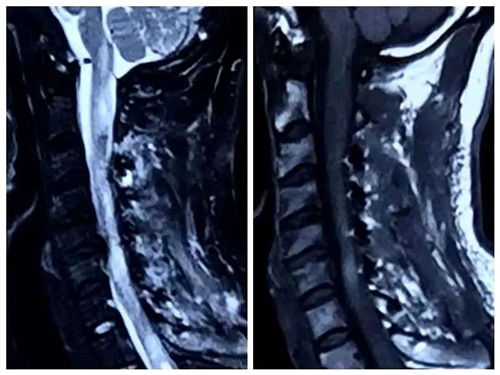

患者术后核磁

三天后,患者接受了显微镜下脊髓髓内肿瘤切除术。经过6个多小时的手术,苏亦兵主任及团队为患者切除了12×2cm大小的肿瘤,手术顺利完成。术后病理提示为室管膜瘤。经过三个月的康复锻炼,现在患者已经可以自如行动,甚至举起哑铃!